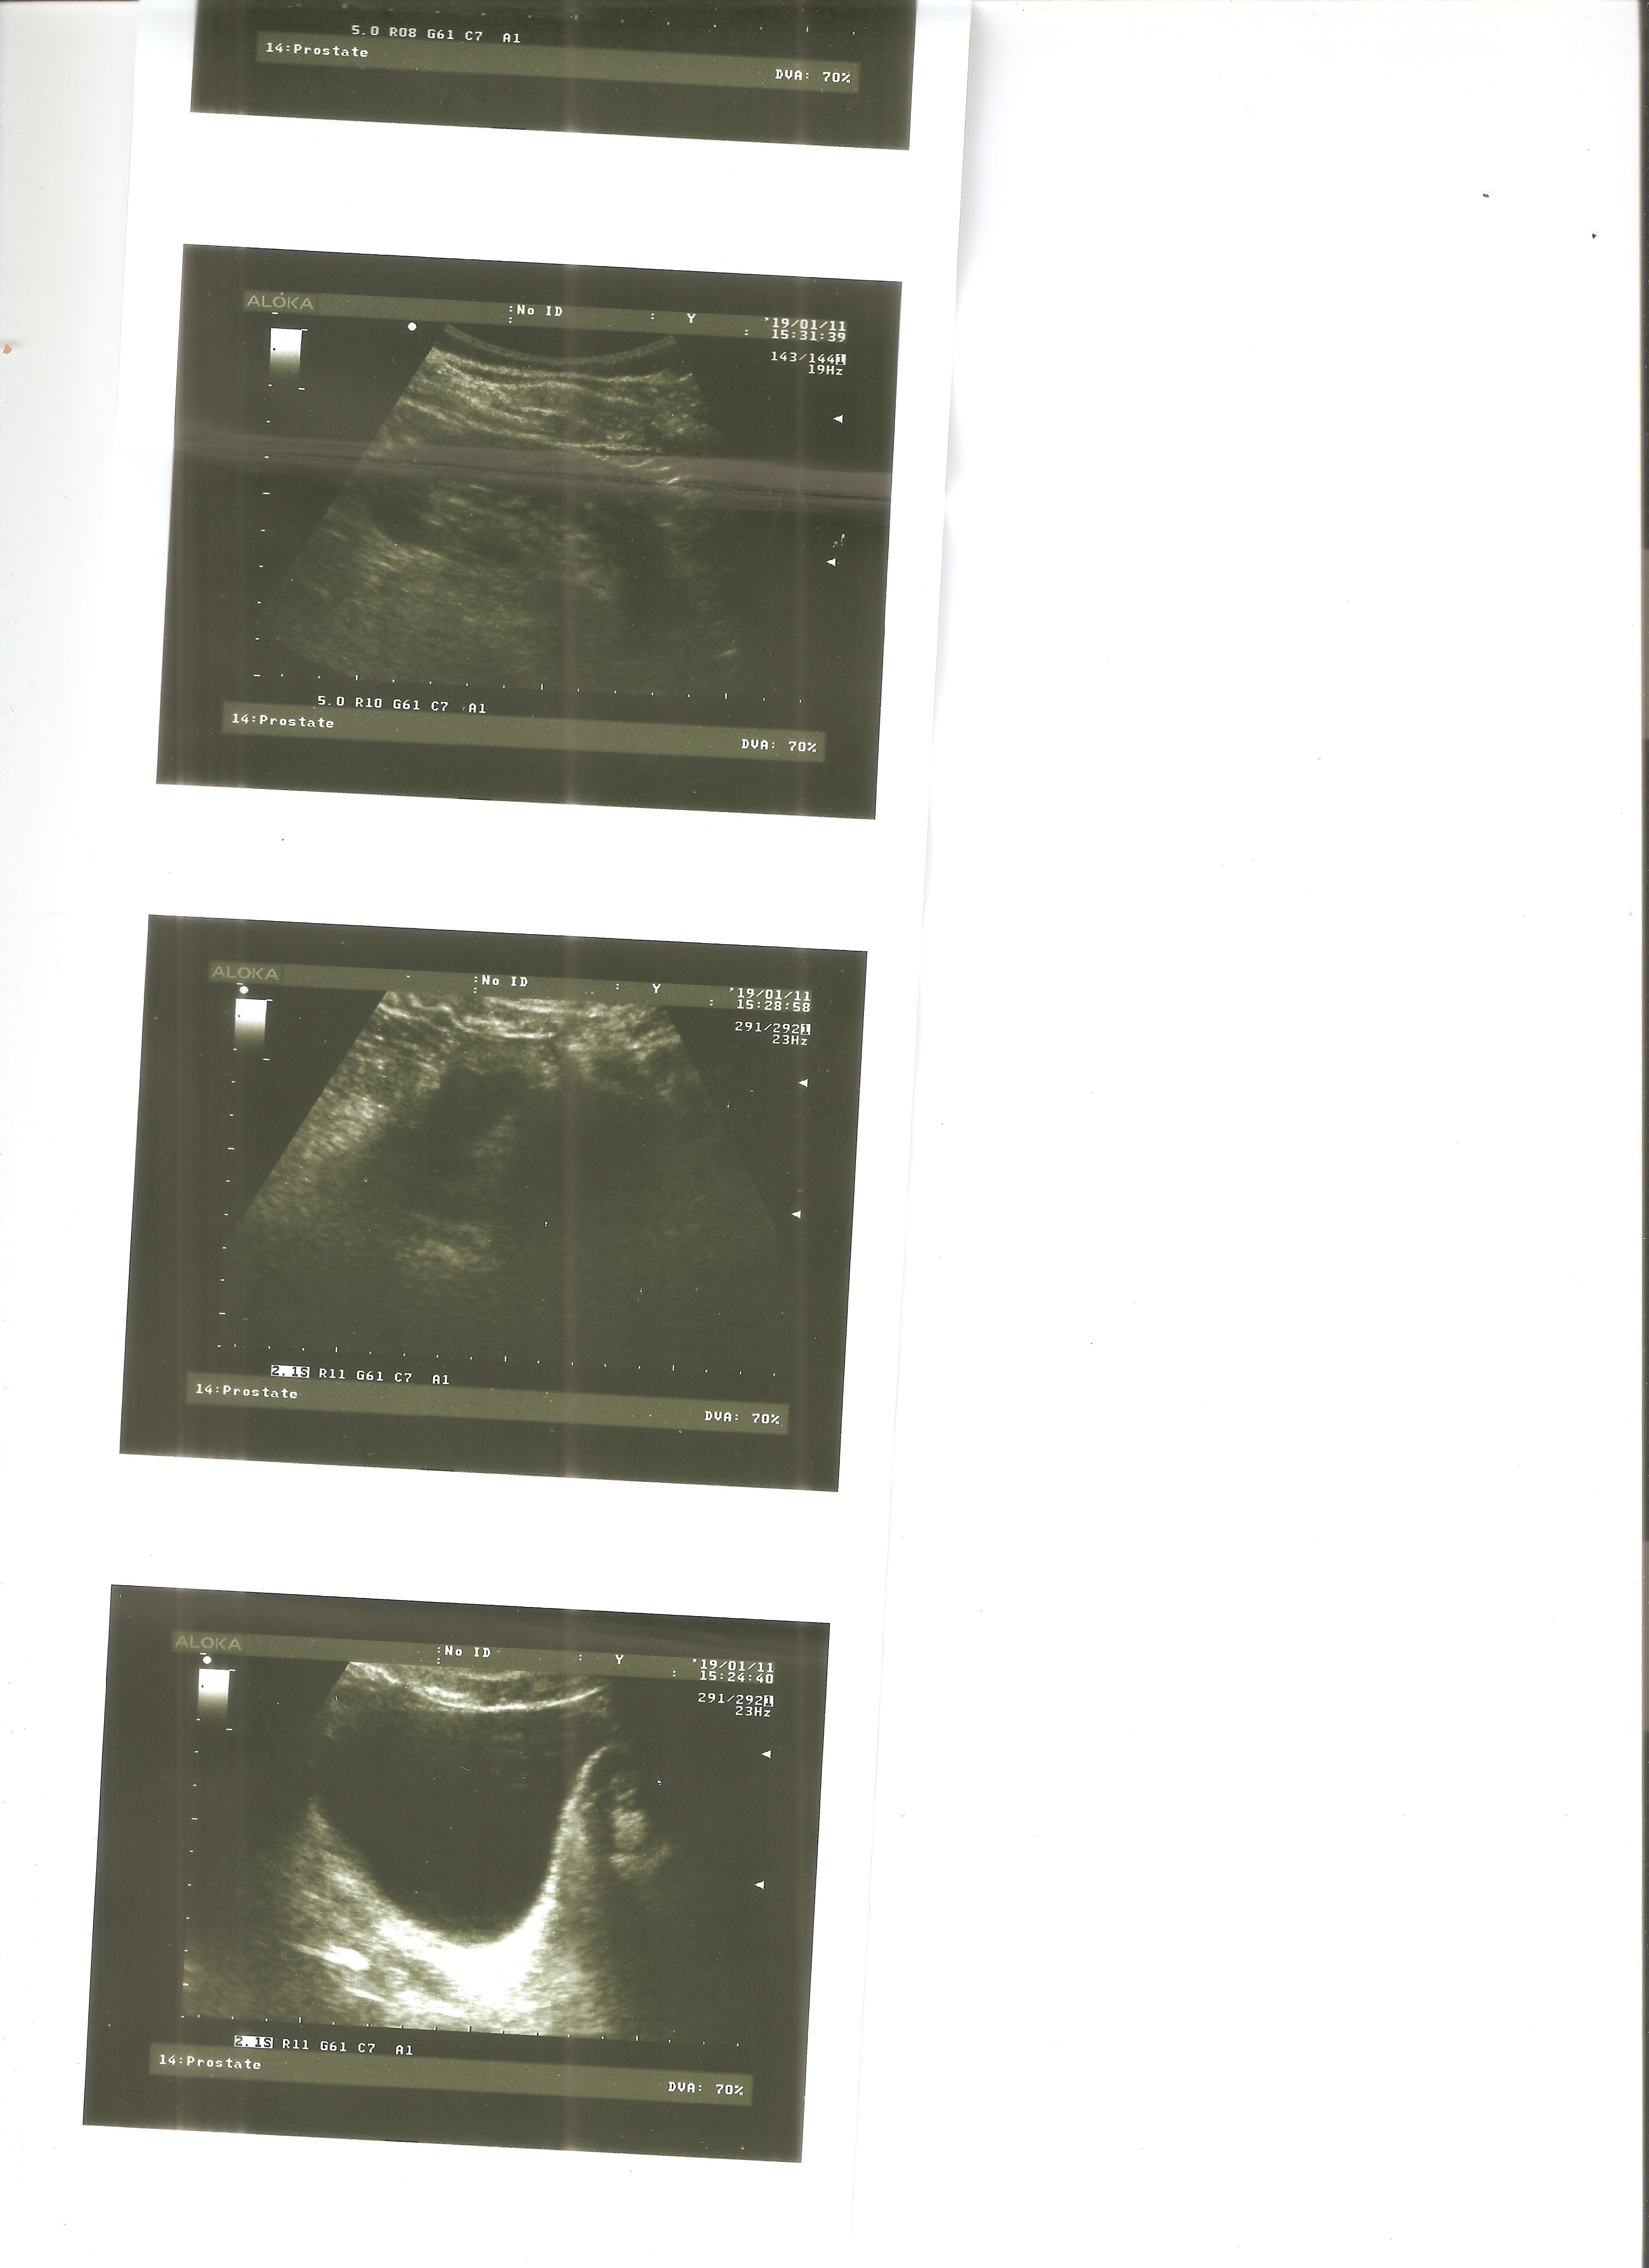

Здравствуйте, вот уже на протяжении полутора лет не могу выяснить причину своего недуга, обошел кучу урологов и венерологов и никто из них не смог мне помочь. Все началось с того, что у меня появилось жжение в уретре после эякуляции, при мочеиспускании боли и жжения не было, только после эякуляции. Походил я по урологам, делал трузи простаты, сдавал на иппп, сдавал секрет простаты и по заверению врачей все у меня нормально. В итоге я не выдержал и самостоятельно проставил себе курс свечей "Виферон" и о чудо, они мне помогли, жжение полностью ушло, но спустя два месяца стал ощущать подергивания в уретре и при пальпации ощущается боль, в основном боль у начала уретры под яичками, но и в середине уретры тоже есть подергивания и покалывания, губки уретры чуть припухшие и красноватые. При мочеиспускании боли нет, эрекция хорошая. Прикрепляю все свежие анализы и исследования к данному сообщению.